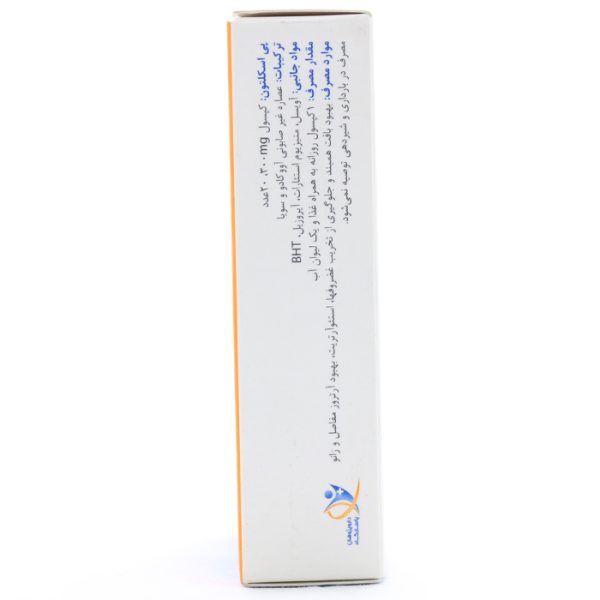

کپسول پی اسکلتون 300

پی اسکلتون ۳۰۰، فرآورده گیاهی جهت کمک به ساخت و ترمیم غضروفها

کپسول پی اسکلتون ۳۰۰، حاوی عصاره غیرصابونی آووکادو و سویا

ترکیبات کپسول پی اسکلتون 300

ترکیبات غیر صابونی حاصل شده از روغن سویا و آووکادو، آویس، منیزیم استئارات، آیروزیل، BHT